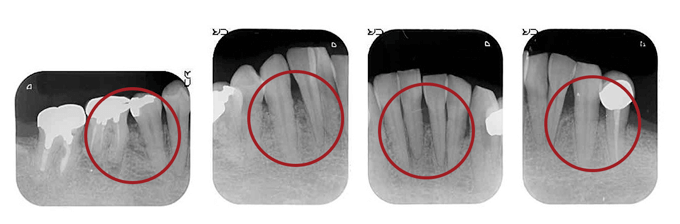

CASE

歯周骨が無くなってしまっていたため、

「骨移植•GTR•エムドゲイン」を使用した40代女性の例

BEFORE(初診時)

赤丸の黒く抜けている部分は歯周病により骨が失われています。

AFTER ( 術後:歯周組織再生療法 )

赤丸の部分に骨移植を行って術後10ヵ月程たった状態です。

黒い部分が白くなってきています。骨が少しずつできてきています。

最初は抜かなければならない可能性の歯もこのように再生療法によって、残す事が可能となります。

治療期間が長くなり、治療費もかかりますが、一生ご自分の歯で生活できるということを考えると、大きなメリットだと思います。

向かって一番右側の奥歯と2番目の歯と3番目の歯の間の骨(矢印)が溶けてなくなっているのがわかるでしょうか?

”噛むと痛んで腫れている、過去に抜歯を薦められ不安なので診てほしい”と来院された女性の患者さんです。

AFTER ( 術中・術後 )

GTR法とエムドゲインの併用による再生療法により骨を再生しました(矢印)。

違いが解りますか?骨が再生されています。